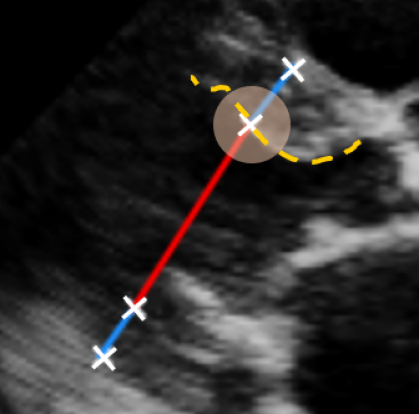

![]() |

|

| (a) LV Measurements | (b) Label Smoothing |

Left Ventricular Hypertrophy (LVH), one of the leading predictors of adverse cardiovascular outcomes, is the condition where heart’s mass abnormally increases secondary to anatomical changes in the Left Ventricle (LV) [10]. These anatomical changes include an increase in the septal and LV wall thickness, and the enlargement of the LV chamber. More specifically, Inter-Ventricular Septal (IVS), LV Posterior Wall (LVPW) and LV Internal Diameter (LVID) are assessed to investigate LVH and the risk of heart failure [21]. As shown in Figure 1 (a), four landmarks on a parasternal long axis (PLAX) echo frame can characterize IVS, LVPW and LVID, and allow cardiac function assessment. To automate this, machine learning-based (ML) landmark detection methods have gained traction.

It is difficult for such ML models to achieve high accuracy due to the sparsity of positive training signals (four or six) pertaining to the correct pixel locations. In an attempt to address this, previous works use 2D Gaussian distributions to smooth the ground truth landmarks of the LV [9, 13, 18]. However, as shown in Figure 1 (b), for LV landmark detection where landmarks are located at the wall boundaries (as illustrated by the dashed line), we argue that an isotropic Gaussian label smoothing approach confuses the model by being agnostic to the structural information of the echo frame and penalizing the model similarly whether the predictions are perpendicular or along the LV walls.